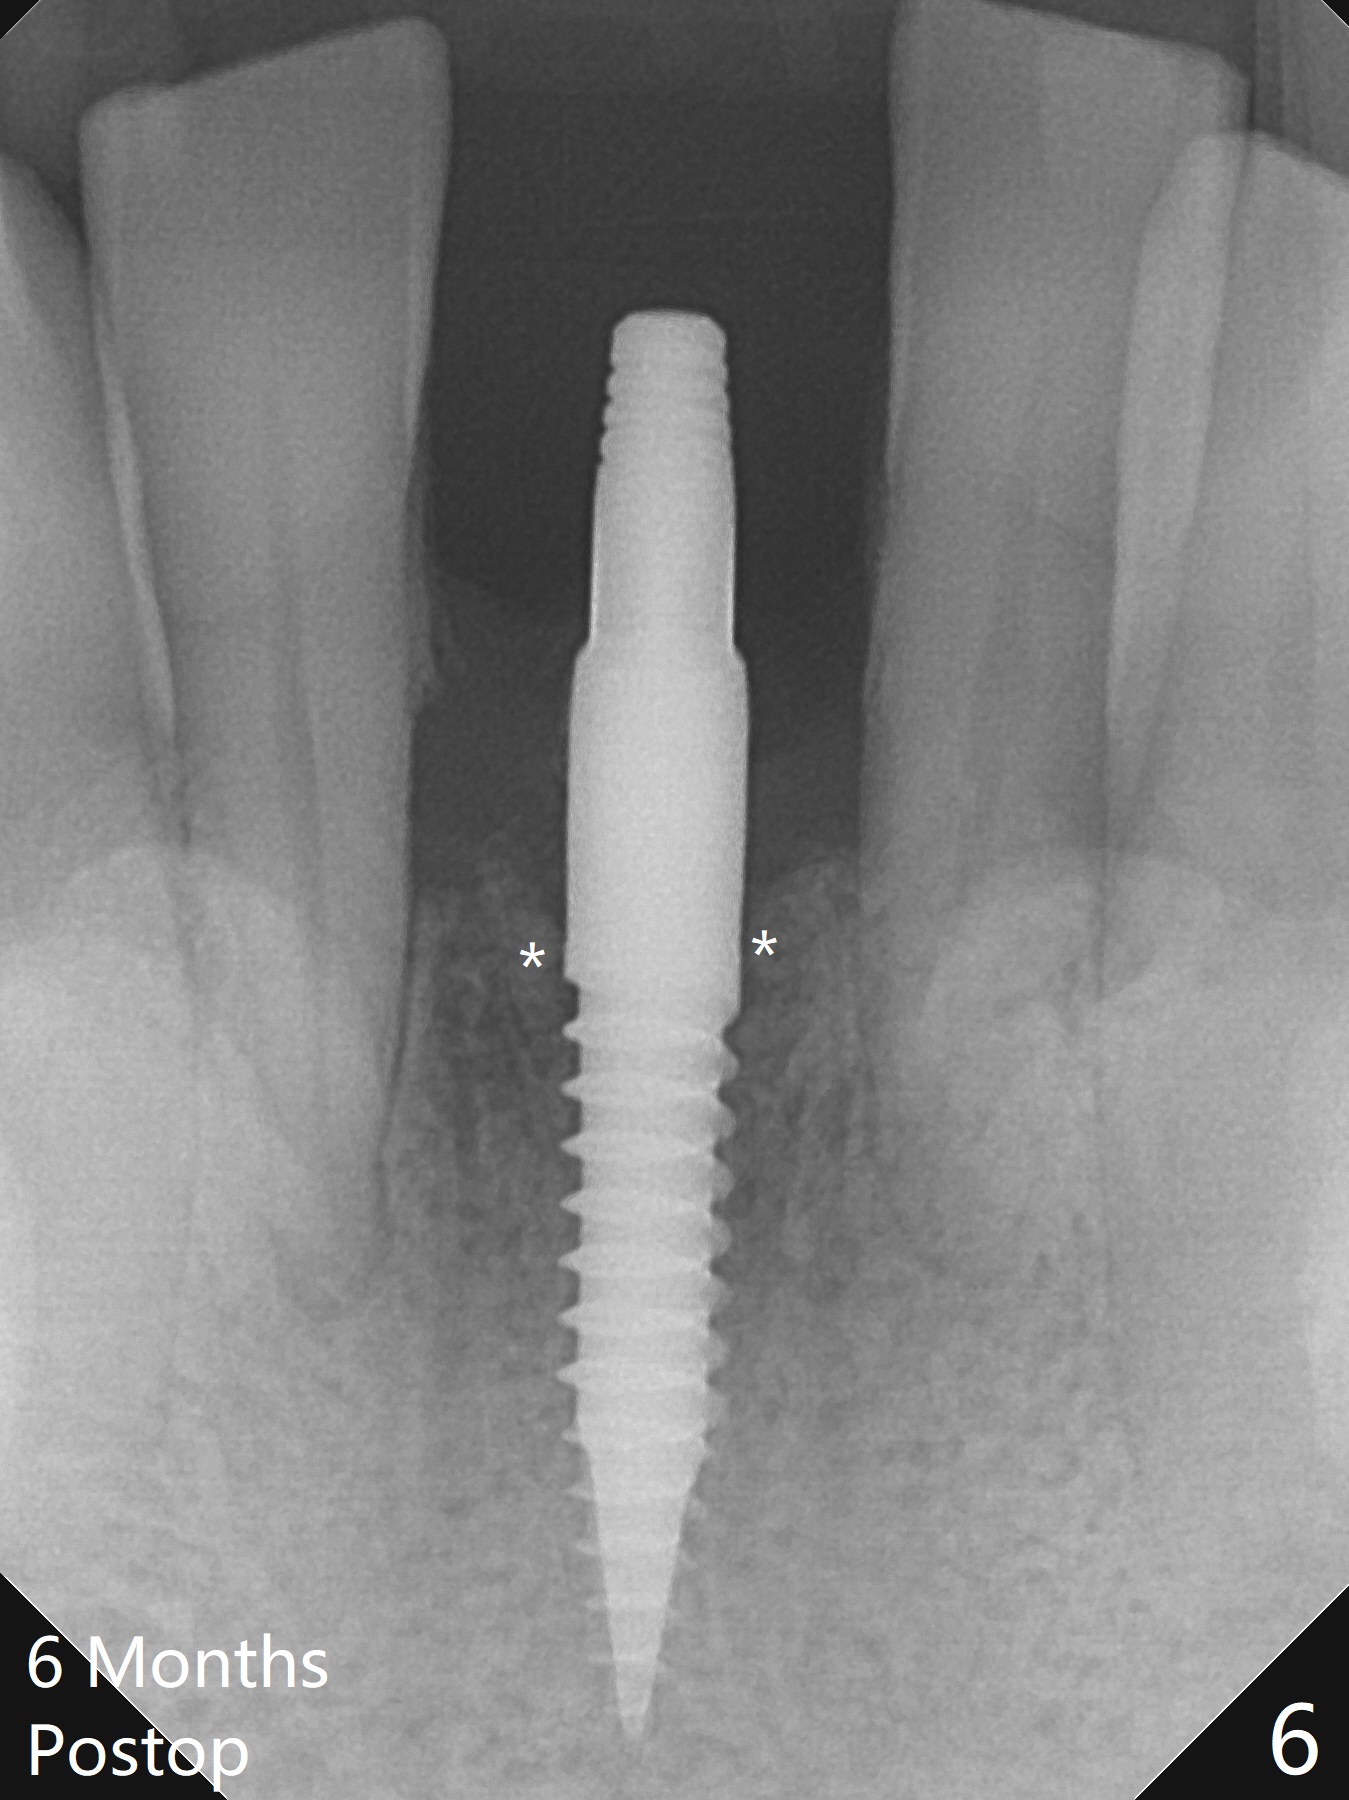

When the patient returns for implant placement 1.5 years after the last treatment (SRP), the tooth #25 has exfoliated, whereas the tooth #24 is severely displaced (Fig.1-3).  In fact the buccolingual plates are found to be lost after extraction, corresponding to change in gingival color indicated by an arrowhead in Fig.1.  Initial osteotomy with 1.2 mm drill is parallel to the terminal branches of the Incisive Canal (Fig.4 arrowheads).  Since the gingiva is as thick as 7.5 mm (Fig.3 arrow), a 3x14 mm 1-piece implant with 4 mm cuff is placed (Fig.5); three implant threads are outside the native bone; with allograft (*) placed and the neighboring crests being coronal to the threads, the chance of periimplantitis should be remote.  An immediate provisional is fabricated to contain the graft in place.  Meanwhile the tooth #2 is symptomatic with crack.  The top 3 threads appear to be contacted by the newly formed crestal bone 6 months postop (Fig.6 *).  Bone appears to have grown into the space between implant threads 6 months post cementation (13 months postop).